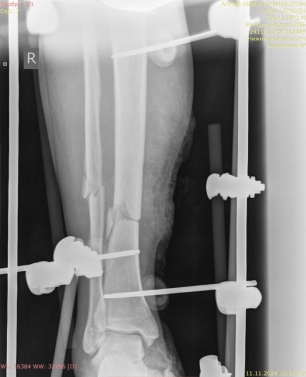

2) Мужчина, 57 лет. В результате падения бревна на область голени получил травму — открытый оскольчатый перелом верхней трети диафиза правой большеберцовой кости со смещением отломков (рис. 4).

Рис. 4.

Ввиду выраженного отечного синдрома в области перелома была выбрана методика конверсионного остеосинтеза, в экстренном порядке выполнены ПХО раны, фиксация перелома аппаратом внешней фиксации, назначена антибиотикотерапия (рис. 5).

Рис. 5.